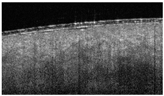

3.1. Epidermis

OCT of uninjured skin showed the epidermis as a dark band (Figure 1a) with a relatively smooth surface, and fine wrinkles were observed in areas of very pliable skin overlying the articulations. The dermo–epidermal junction was marked by a visible step from dark grey (epidermis) to light grey (dermis).

OCT visualization of the epidermis in healthy skin (a) and thermally injured skin (b): epidermis/loss of epidermis (double arrow), DEJ (star), and surface irregularity (simple arrows).

Surface irregularity (Figure 1) is a characteristic, universal feature of all wounds and was present in each wound. Blistering occurs near the dermo–epidermal junction (DEJ) and causes the disappearance of the dark band in the OCT image (Figure 1b). Both signs are easily identified, and each results in a score of 1.